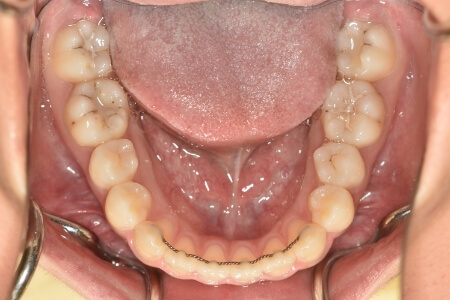

開咬(非抜歯)【2137】

動的治療終了時

症例 症例 症例 症例 症例

治療としては、非抜歯の上、マウスピース型矯正装置(インビザライン)で配列を行いました。顎間ゴムの協力もあり、開咬、中心のズレがきれいに改善されました。